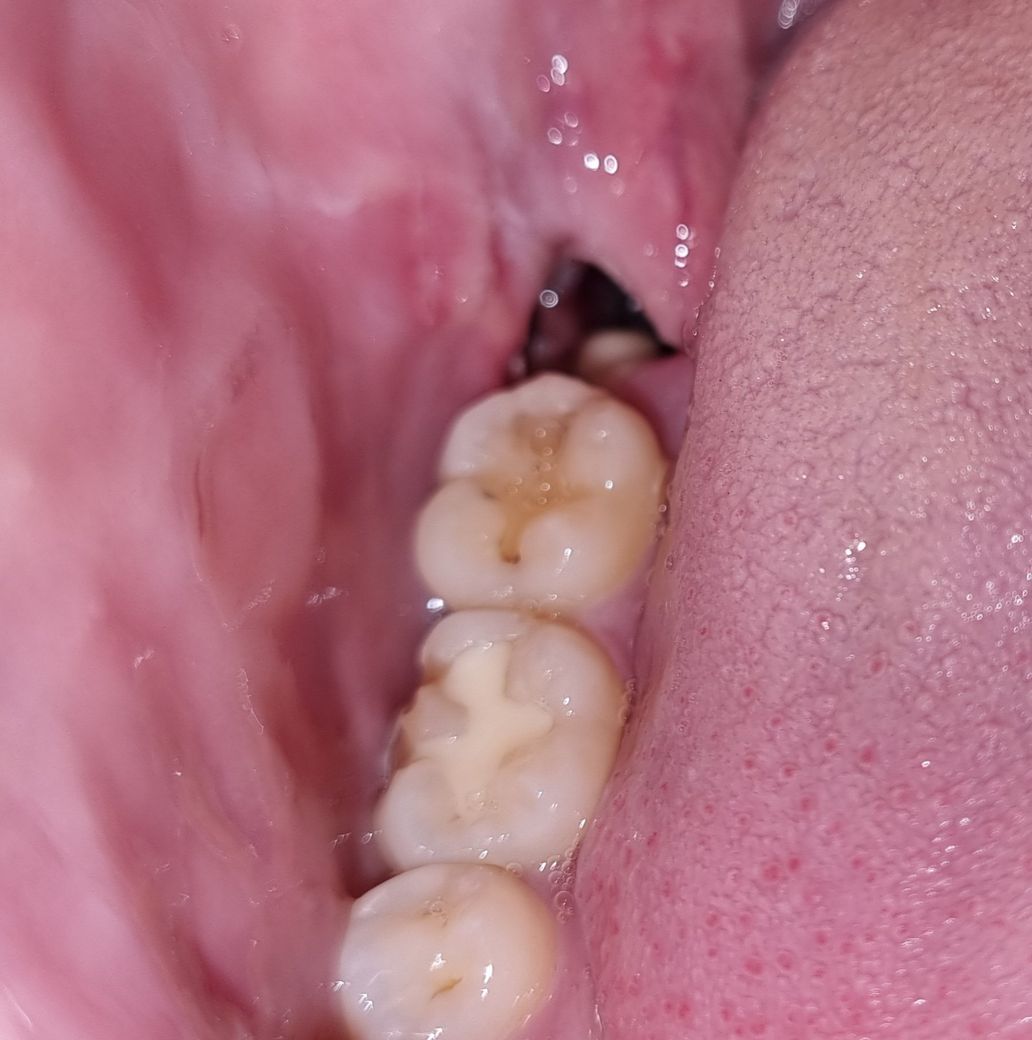

사랑니 발치 후 뼈가 보입니다 정상인가요?

사랑니 발치 후 이제 3일이 됩니다.

지금까지 큰 붓기나 큰 통증 없이 잘 지냈는데 문득 오늘 거울을 보니까 뼈가 보이는 것 같아서 걱정이 됩니다.

사진처럼 뼈가 보이는 것 같아서 걱정에 질문드립니다.

• 1번 째 사진

사진상 보이는것은 뼈라기보다는 혈병과 음식물이 섞인 거죽으로 판단됩니다.

무엇보다도 뒤에서 두번째 예전에 GI재료로 떼우신 곳 치아가 떨어져 나가서 문제가 될 가능성이 높아 보이니 크라운 등의 치료를 받으시는게 좋겠습니다.~

사진으로 보이는것은 뼈가 아니라 음식물이나 음식물찌꺼기 또는 잇몸의 일부분이 하얗게 보이는 것으로 보입니다.

약간 희게 보이는 것은 뼈가 아니라 잇몸부위에 하얗게 딱지 앉은 것으로 보입니다.

그리고 이가 빠진 부위에 웅덩이 파진 것도 정상적인 것입니다.

사랑니 발치가된 발치와에 뼈가 보일수도 있습니다. 크게 문제가 되는건 아닙니다. 다만 저 공간에 음식물이 남아 있지 않도록 식사를 하시고 잘 헹궈주시는게 좋습니다.